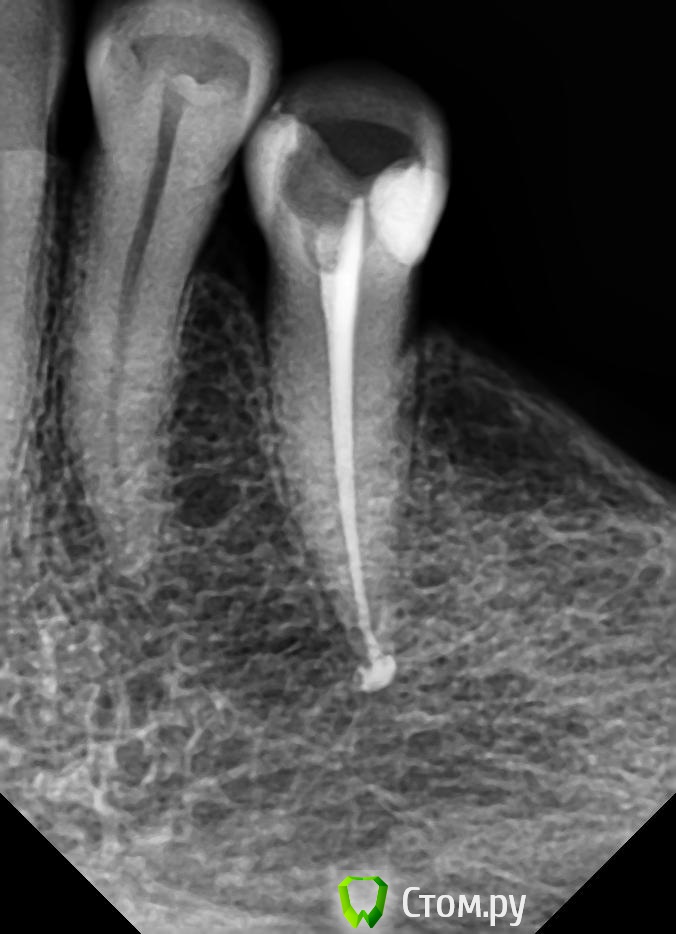

Л-Ф Опубликовано 2 апреля, 2014 Автор Поделиться Опубликовано 2 апреля, 2014 (изменено) У Вас должны быть еще снимки, после удаления нерваК сожалению,ни ДО ни ПОСЛЕ мне не делали снимки.Это я уже в платной сегодня сделала.Сейчас стоит временная,белая пломбаЭти снимки с временной пломбойДобавлю,что зуб немножко подвижный...немногоЕще вопрос.Удален ли у меня нерв полностью?И в сом низу зуба очертания какие то....может там воспаление? или мне кажется Изменено 2 апреля, 2014 пользователем Л-Ф Ссылка на комментарий

Л-Ф Опубликовано 23 апреля, 2014 Автор Поделиться Опубликовано 23 апреля, 2014 (изменено) Синяк у Вас, это гематома после укола, такое бывает... пройдет. Корневой канал еще не запдомбирован, поэтому сказать, что то о качестве не могу. Един ственный момент который сильно смущает это отсутствие снимков в процессе работыЗдравствуйте! Одним словом я обращалась далее в Стоматологическую больничку,в смотровой кабинет.По поводу ноющей боли.Мне убрали временную пломбу,почистили и закрыли опять временной пломбой.Боль сразу прошла и все было замечательно.Вот теперь 21 числа сходила и поставили постоянную пломбу.Вроде сразу ничего не болело при надкусывании на зуб сутки.А теперь появилась второй день боль при надкусывании острая и так ноющая немного,голова болит.Посмотрите пожалуйста снимок и дайте совет.Как мне быть.Однозначно у врача кривые руки.Что-то у нее не получается по хорошему.Почему,когда она мне запихивала пломбу в каналы у меня была боль,ведь мне убрали нервы.Почему сейчас вновь появилась боль ,по ощущению в корне зуба?Один снимок с временой пломбировкой,другой еще не совсем закрыт,только канал.Потом закрылиНомер зуба 35 Изменено 23 апреля, 2014 пользователем Л-Ф Ссылка на комментарий

sydnik Опубликовано 23 апреля, 2014 Поделиться Опубликовано 23 апреля, 2014 Здравствуйте!не ругайте врача(наверное долго лечила, вас это и насторожило ,ведь раньше пару минут и все готово ) ,по снимку все красиво,боль пройдет через пару дней 1 Ссылка на комментарий

Гарриевич Опубликовано 23 апреля, 2014 Поделиться Опубликовано 23 апреля, 2014 Снимок нормальный Болевые рецепторы у нас есть не только в нерве зуба, они есть еще и вокруг корня и где их только нет поэтому чувствовали боль когда материал выходил за верхушку корня, это ничего страшного, все пройдет Ссылка на комментарий

Л-Ф Опубликовано 23 апреля, 2014 Автор Поделиться Опубликовано 23 апреля, 2014 Вот я сделала Контраст снимка в программе и увидала,что плохо запломбировано внизу у корня....... Проверьте,кто-нибудь хорошенько.Боль острая.при смыкании зубов Ссылка на комментарий

Л-Ф Опубликовано 24 апреля, 2014 Автор Поделиться Опубликовано 24 апреля, 2014 Вот пожалуйста,сделала фото корня зуба с Контастом.Тут ясно видно плохое заполнение.Как вы считаете? Жду советы Ссылка на комментарий

red_butler Опубликовано 24 апреля, 2014 Поделиться Опубликовано 24 апреля, 2014 канал нормально запакован Ссылка на комментарий

Гарриевич Опубликовано 24 апреля, 2014 Поделиться Опубликовано 24 апреля, 2014 В пределах канала корня все плотно запломбировано Ссылка на комментарий